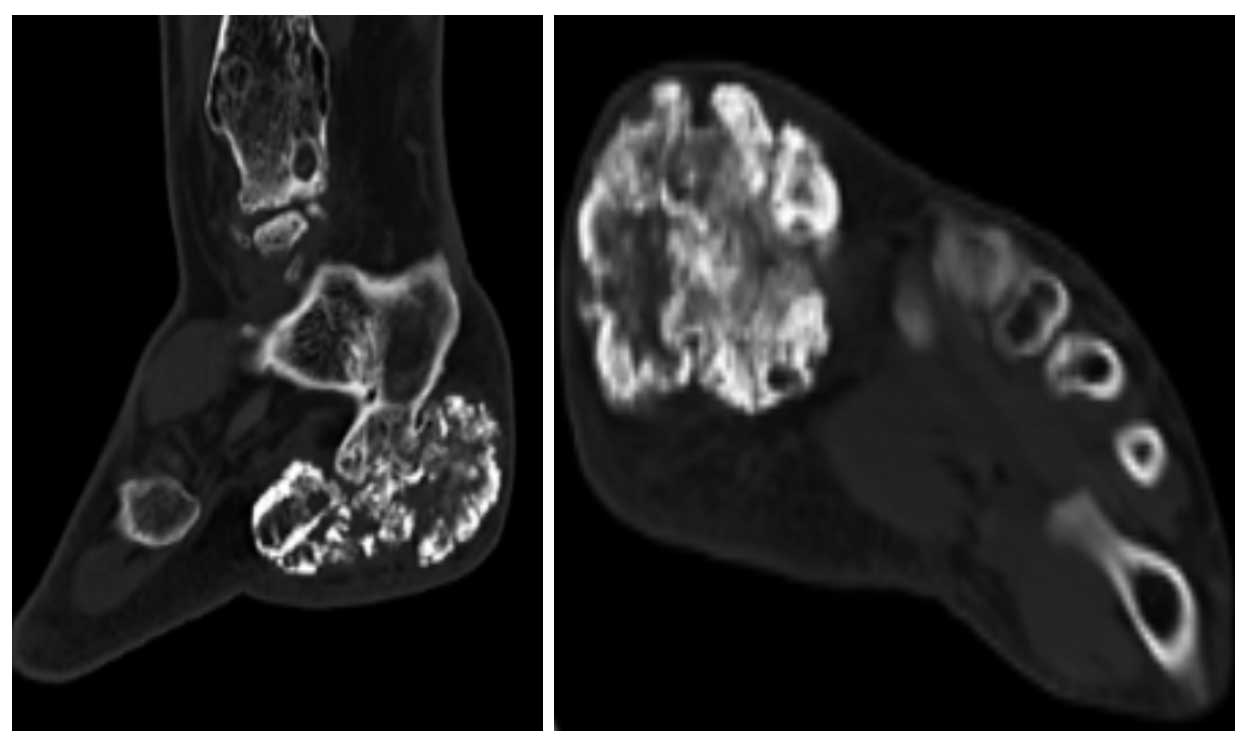

Ameliyat Öncesi: Tomografide düzensiz sınır ve içerikli tümör dokusu görülmekte.